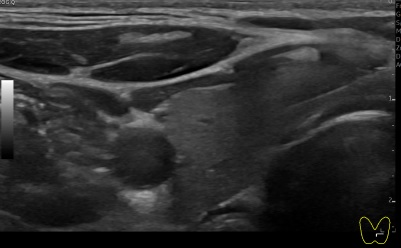

상기환자 갑상선 추적관찰 하시는 40대 초반 여성분으로 갑상선 초음파 시행후 의심스러운 갑상선 좌엽 결절 세포검사 진행후 갑상선암으로 진단되었습니다